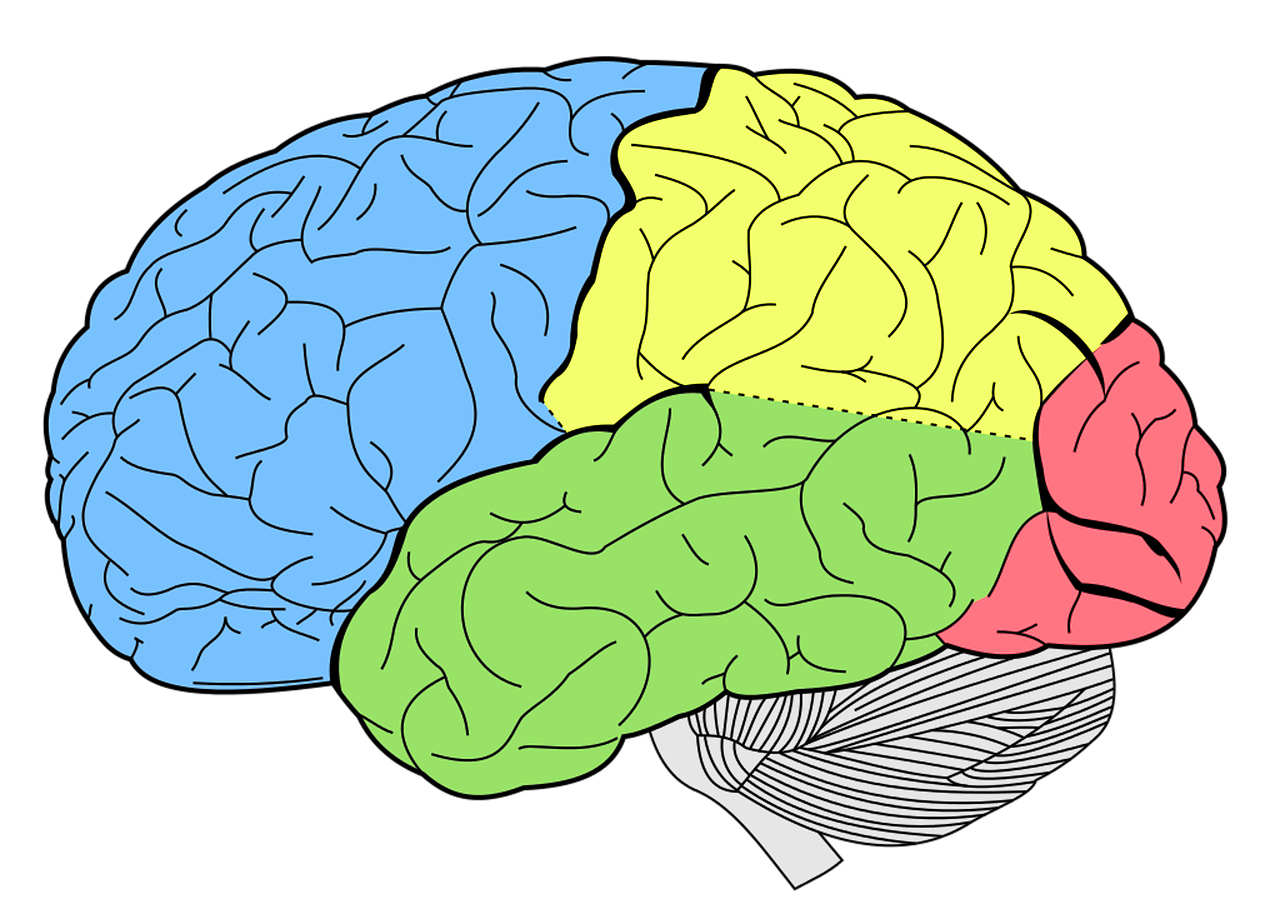

Fumo, pressione alta, diabete e obesità sono tra i fattori di rischio che pesano anche sulla salute del cervello oltre che su quella cardiovascolare, contribuendo a indurre modifiche in aree chiave per le funzioni cognitive superiori come memoria e ragionamento, aree il cui deterioramento è particolarmente implicato nell'Alzheimer.

È emerso che a parità di età, sesso e altri fattori che possono condizionare lo stato di salute del cervello, presentare un elevato rischio vascolare si associa a una riduzione del volume della materia grigia di 18 millimetri (praticamente un volume pari a quello di un tubetto di dentifricio da viaggio), ovvero del 3%, rispetto a coloro che non hanno fattori di rischio vascolari. Ad essere coinvolte sono primariamente aree neurali importanti per le funzioni cognitive superiori e la memoria.